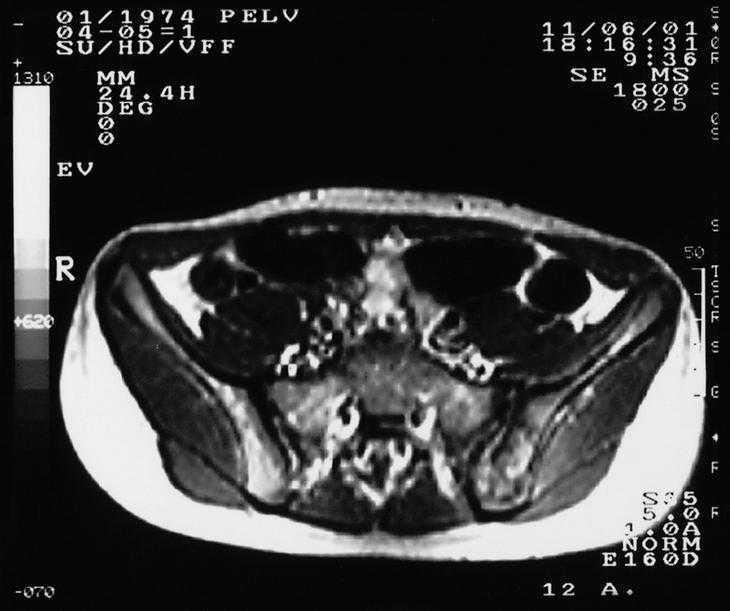

Se realizó analítica completa que incluyó hemograma, bioquímica con enzimas hepáticas, calcio, fósforo, fosfatasa alcalina, proteinograma, alfa-1-antitripsina, inmunoglobulinas y función renal, cuyos valores estuvieron dentro del rango de la normalidad. La velocidad de sedimentación globular (VSG) fue de 40 mm. La radiografía de tórax y la ecografía abdominal no evidenciaron alteraciones. En la radiografía de las sacroilíacas se observó una sacroilíaca izquierda con márgenes irregulares y mal definidos (fig. 1). En la gammagrafía con 99mTc se describió una lesión localizada en la sacroilíaca izquierda que deformaba y superaba esta articulación, con bordes abollonados hipercaptantes de forma moderada y áreas frías centrales. Se llevó a cabo una tomografía axial computarizada (TAC) de las sacroilíacas que puso de manifiesto alteraciones en la arquitectura trabecular del hueso ilíaco izquierdo con focos de lisis y esclerosis ósea adyacente a la articulación (fig. 2). En la resonancia magnética (RM) de las sacroilíacas se observaron cambios en la intensidad de la señal del componente medular de la pala ilíaca izquierda, con alternativa de hipo e hiperintensidad, y asimetría tenue de partes blandas con leve aumento de volumen en las zonas próximas al hueso sugestivo de proceso infiltrativo tumoral (fig. 3). En la TAC torácica se describió una imagen nodular en el lóbulo inferior izquierdo en los segmentos posteriores compatible con metástasis pulmonar. La biopsia de médula ósea no mostró signos de infiltración neoplásica. Se realizó una biopsia de la lesión que evidenció un tumor indiferenciado de célula redonda pequeña, con afección de hueso, periostio y músculo esquelético así como la presencia de fibrosis y desmoplasia estromal notables, sin signos de diferenciación. Los marcadores CD45, PAS, proteína S-100 y desmina fueron negativos. Se observó también manifiesta positividad de membrana para el anticuerpo CD-99 (O13), vimentina + + + y ENS (enolasa neuronal) + /-. Este patrón fue compatible morfológica, histoquímica e inmunocitoquímicamente con tumor de Ewing.

Figura 1. Radiografía de sacroilíacas. Se observa la sacroilíaca izquierda con márgenes irregulares y mal definidos.